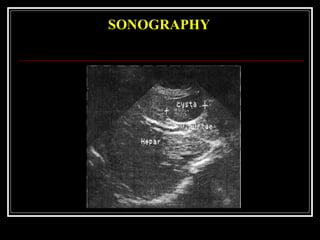

 SONOGRAPHY examination shows echofree formation

SONOGRAPHY

CLINICAL MANAGEMENT  PAIN(dull, permanent, cramp-like and belt-like). It is localized in right hypochondrium, epigastric area, left hypochondrium Pain radiates into the back, left shoulder-blade, shoulder and spine.  DYSPEPSIA characterised by nausea and vomiting.  FUNCTIONAL INSUFFICIENCY OF PANCREAS by disorders of exocrine and endocrine insufficiency, alternating diarrhea with constipation, steatorrhea and creatorrhea, secondary diabetes  COMPRESSION SYNDROME. As a result of compression of neighbouring organs are: partial obstruction of common bile duct (mechanical jaundice), veins (portal hypertension), splenic vein (splenomegaly)  During the CLINICAL EXAMINATION patients with large cysts there is marked asymmetry of abdomen in the epigastria and mesogastric areas.  SONOGRAPHY examination shows echofree formation

A contrast-injected CT-scan reveals active bleeding (B) into a pseudocyst (arrows)